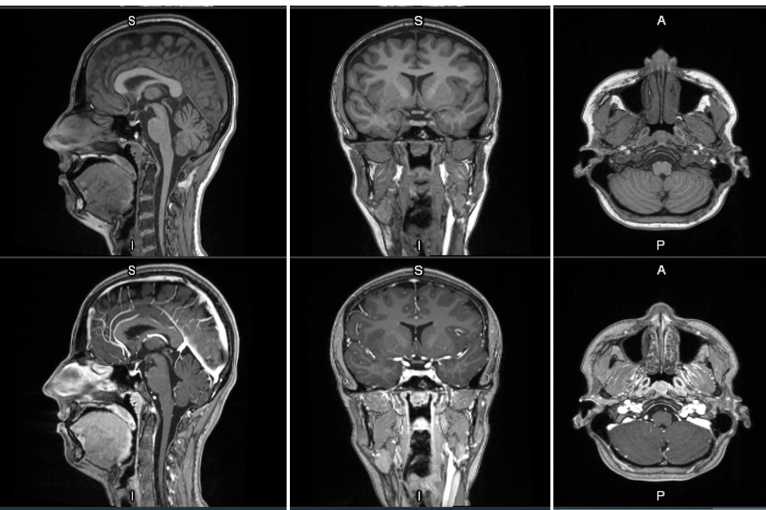

MRI contrast agents enhance the visualization of abnormal structures or lesions during imaging procedures and help clinicians better distinguish between healthy and diseased tissue. Mangaciclanol is intended for general-purpose MR imaging and demonstrates comparable relaxivity (the ability to enhance signal intensity) to market-leading gadolinium-based agent, gadobutrol, with early clinical images suggesting similar diagnostic capability. Unlike gadolinium, which is a rare-earth metal, manganese is present in our food, and is an endogenous element, naturally occurring and autoregulated in the body. The macrocyclic ‘cage-like’ structure of mangaciclanol lessens the possibility of retention.